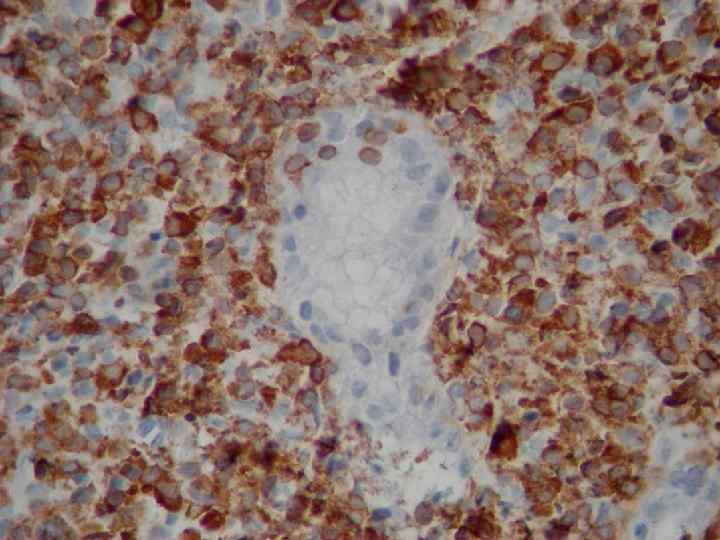

Микропрепараты: Лимфогранулематоз и Нодулярный Склероз